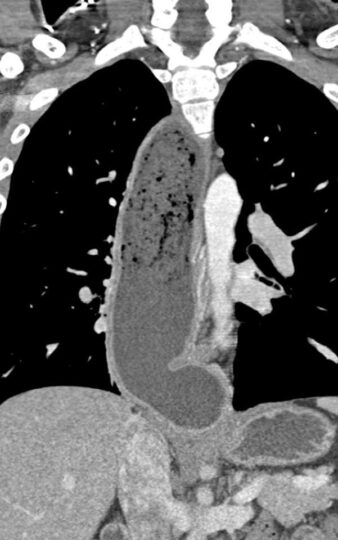

TC DE TORAX .

La Acalasia es un trastorno poco frecuente, que dificulta el paso de alimentos y líquidos hacia el estómago. La acalasia se presenta cuando se dañan los nervios del esófago. En consecuencia, el esófago pierde la capacidad de empujar el alimento hacia abajo, y la válvula muscular que se encuentra entre el esófago y el estómago( esfínter esofágico inferior) no se relaja por completo, lo que dificulta que el alimento llegue al estómago.